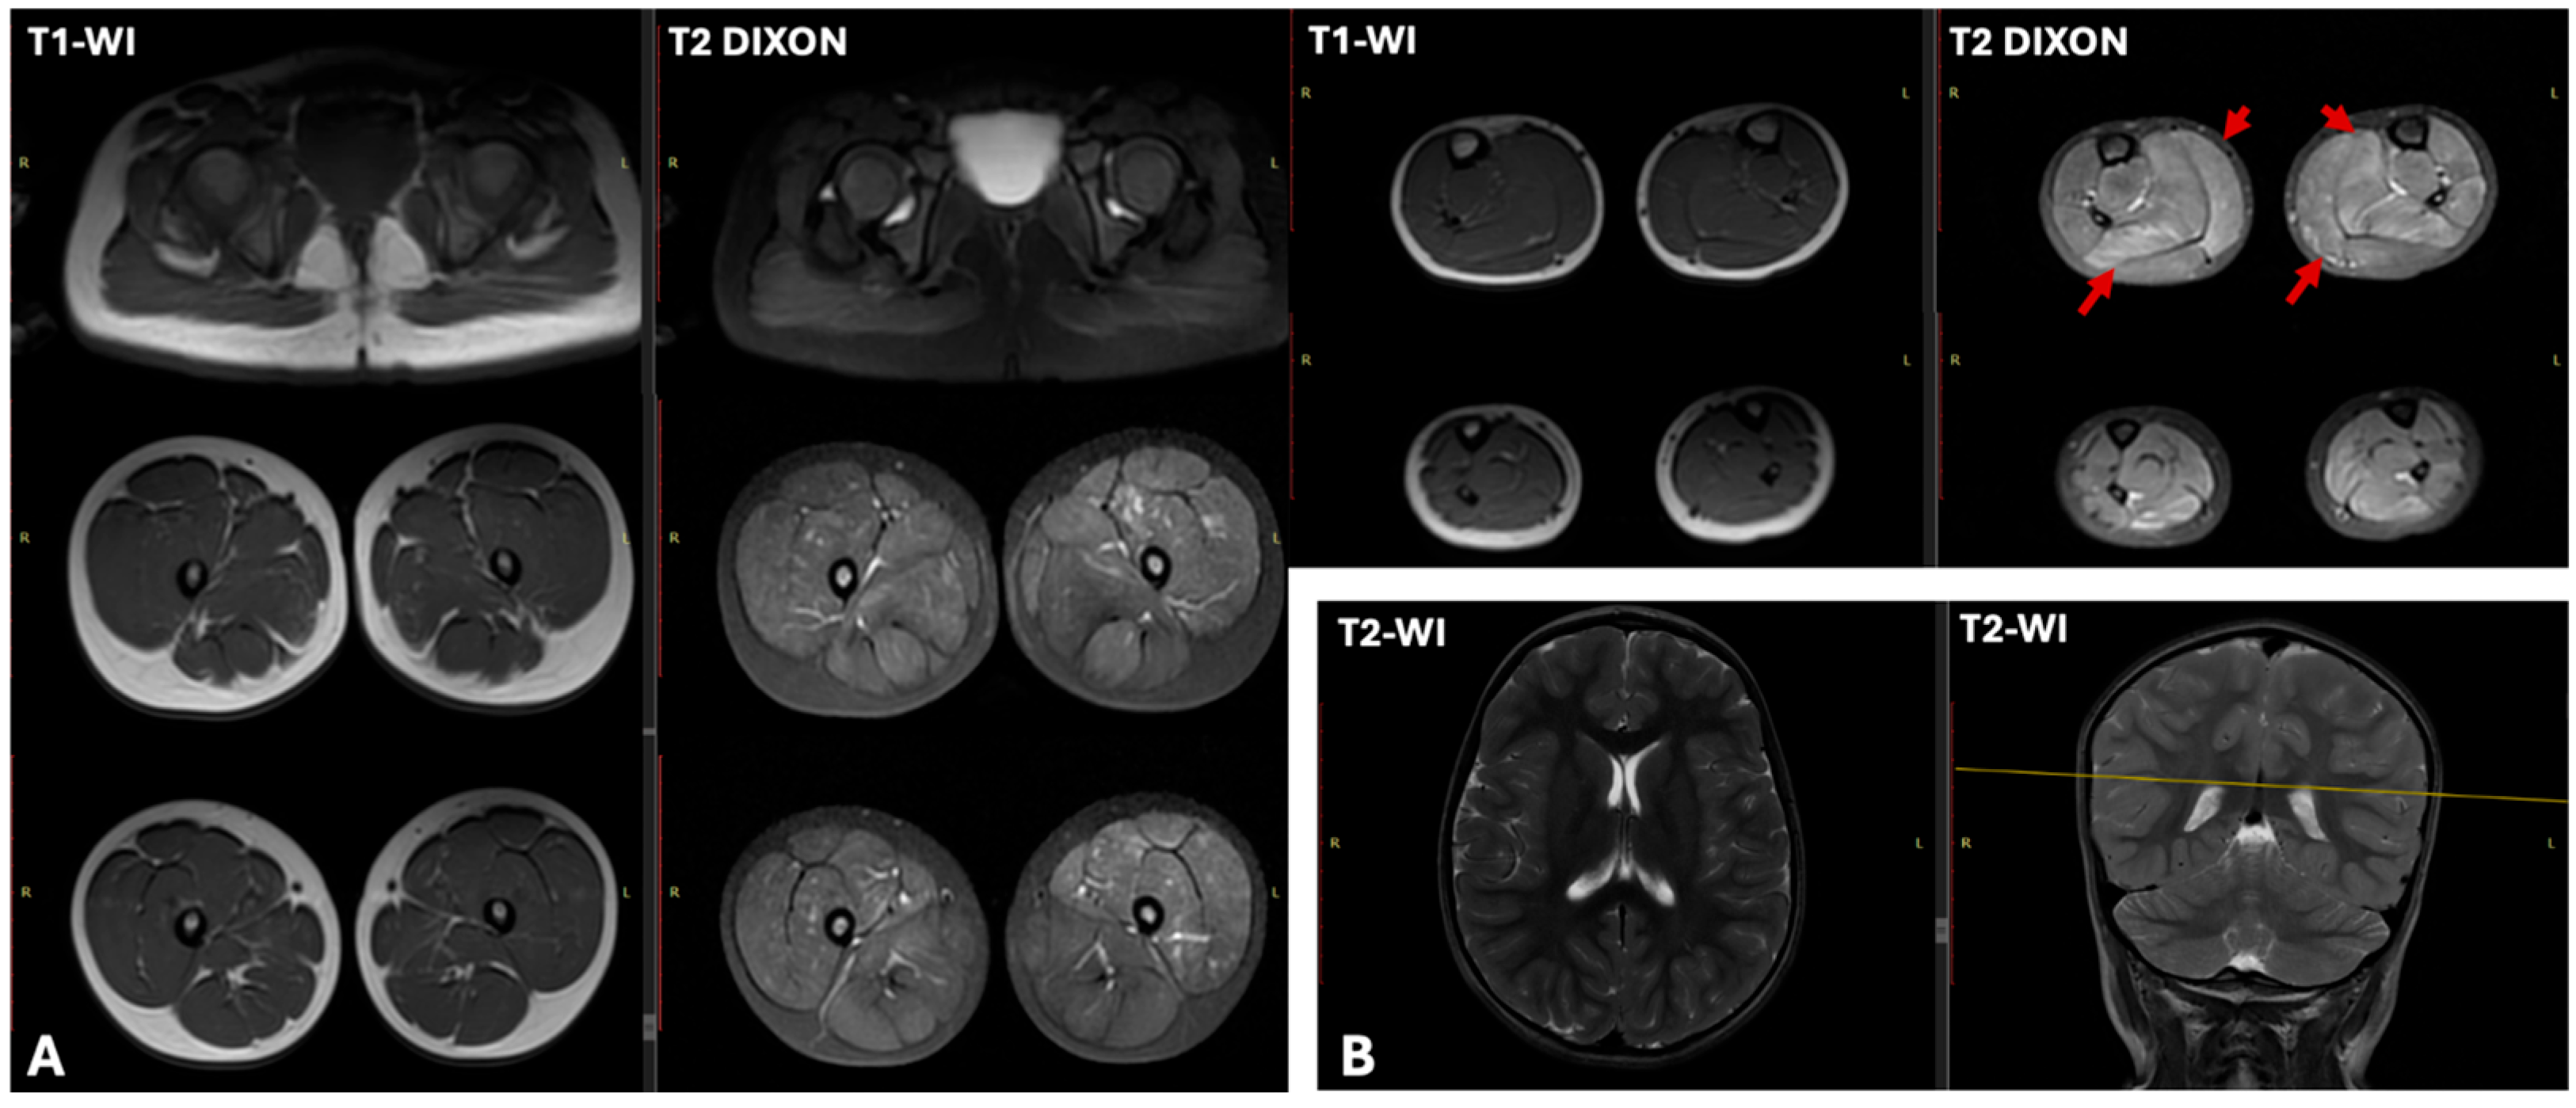

| Patient | CK (U/L) | ALT and AST (U/L) | ECG | Cardiac US | Lower Limb Muscle MRI | EMG |

|---|---|---|---|---|---|---|

| N1 | 26,694 | x11 | Moderate sinus arrhythmia, incomplete RBBB. Deep Q wave in leads III and aVF. Slight impairment of repolarization in the myocardium, manifested as T wave flattening in lead III | LVEF—61.4% (normal >60%), LVEDD—37.4 mm (normal <37 mm). | T1-WI showed no fatty infiltration. T2 DIXON images revealed clear hyperintensity within the soleus and medial gastrocnemius muscles | myogenic pattern |

| N3 | 16,000 | x3–5 | Abnormal ventricular repolarization | No changes | Characteristic “trefoil with a single fruit” sign, with severe involvement of the adductor magnus and biceps femoris and relative sparing of the gracilis, sartorius, adductor longus, and semitendinosus. | myogenic pattern |